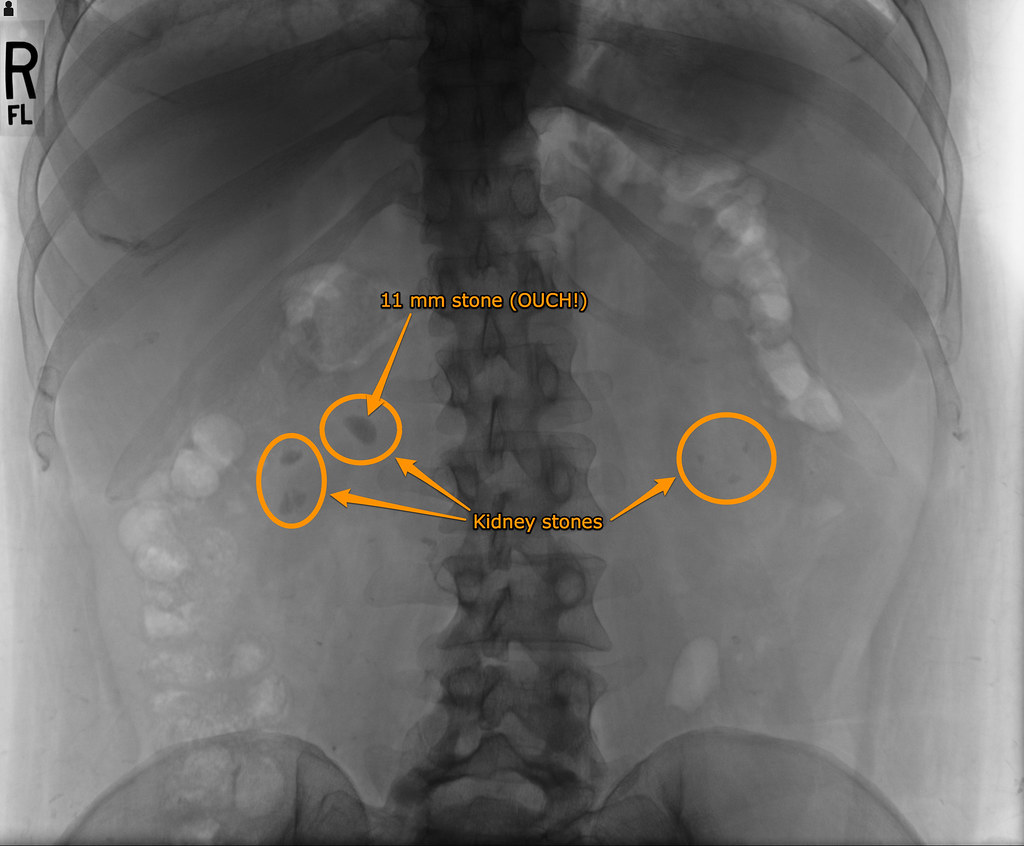

Bust Up Kidney Stones . What is shock wave lithotripsy? Lithotripsy uses sound waves to break up large kidney stones into smaller pieces. Over 1 in 10 men and about 1 in 14 women in the united states will have kidney stones at least once in their lives. Diet, excess body weight, some. Kidney stones (also called renal calculi, nephrolithiasis or urolithiasis) are hard deposits made of minerals and salts that form inside your kidneys. Shock wave lithotripsy (swl) is the most common treatment for kidney stones in the u.s. The most common form of lithotripsy is. Understanding how they form and how they’re. Right now, many kidney stones can be treated with a procedure called shock wave lithotripsy. Extracorporeal shock wave lithotripsy (eswl) is a noninvasive procedure healthcare providers use to treat kidney stones. Kidney stones are a common kidney problem.